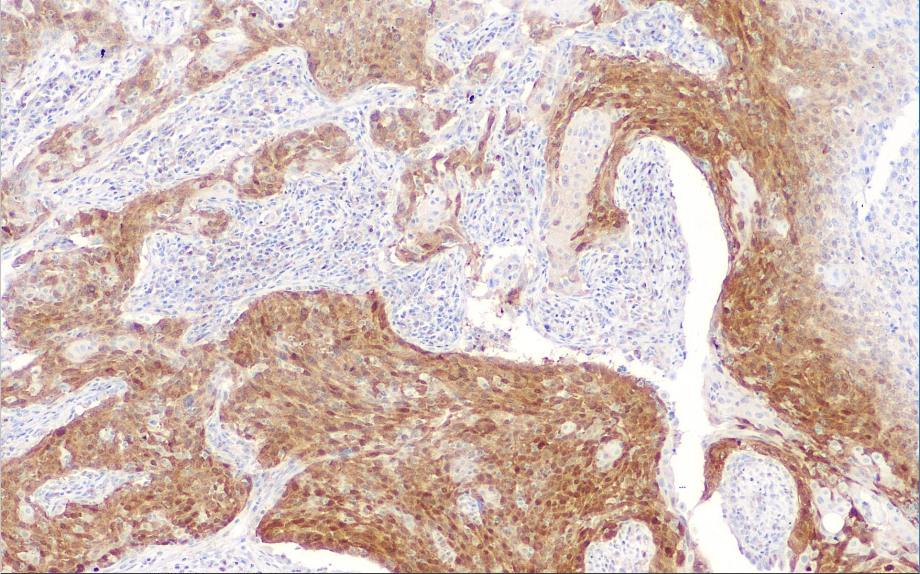

Positive control: Cervical cancer

CDK4 is a cell cycle-dependent kinase that is a regulatory center for the G1-S phase of the cell cycle. The protein is continuously expressed throughout the cell cycle. Phosphorylation of CDK4 is a downstream event of stimulatory or inhibitory cytokine signaling that promotes cellular transformation and cell proliferation in the G1-S phase, and is a point of detection in the middle of the G1 phase, with peak expression of the CDK4 protein in the mid- to late-G1 phase. CDK4 is most closely related to cell carcinogenesis in the process of cell cycle abnormalities. It is overexpressed in many tumors, such as oral cavity squamous carcinoma, esophageal squamous carcinoma, pancreatic islet cell carcinoma, lung cancer, breast cancer, and colon cancer. It is used in combination with MDM2 for the diagnosis of liposarcoma and spindle cell sarcoma.

CDK4 antibody reagents can specifically bind to CDK4 molecular antigens. Immunohistochemistry kits containing CDK4 antibody reagents are suitable for the auxiliary diagnosis of dedifferentiated liposarcoma, cervical cancer, breast cancer, colon cancer, lung cancer, and other diseases.